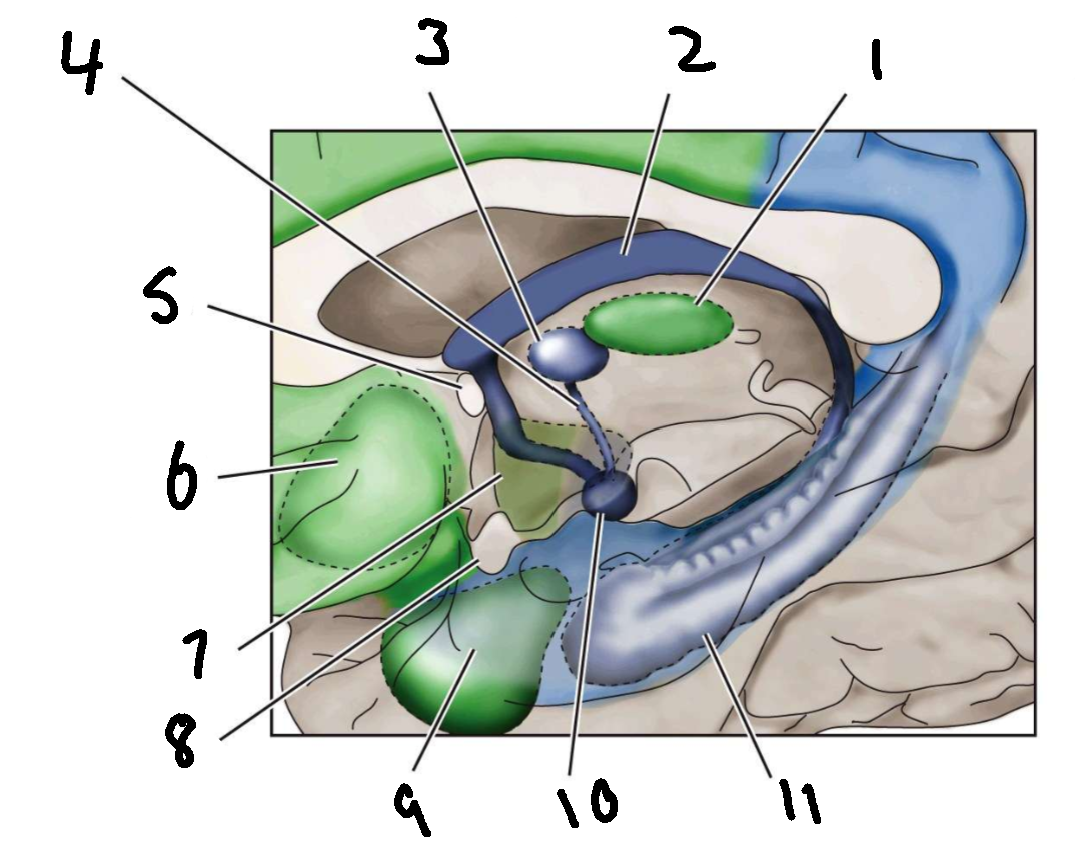

What is 1?

mediodorsal nucleus of the thalamus

What is 2?

fornix

What is 3?

anterior nucleus of the thalamus

What is 4?

mammillothalamic tract

What is 5?

anterior commissure

What is 6?

ventral basal ganglia

What is 7?

hypothalamus

What is 8?

optic chiasm

What is 9?

amygdala

What is 10?

mammillary body

What is 11?

hippocampus